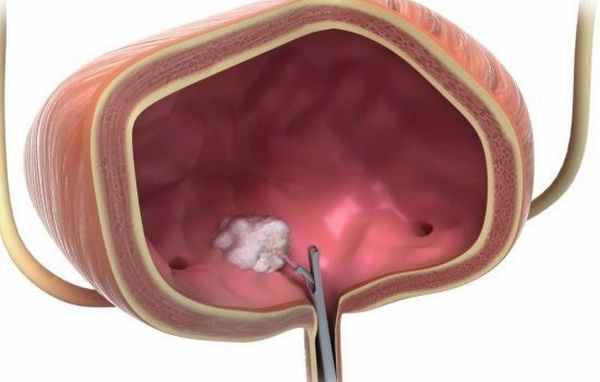

К приобретенным анатомическим причинам необходимо отнести ятрогенное повреждение области мочевого треугольника и устья мочеточника во время ТУР мочевого пузыря или рассечение устья мочеточника при экстракции камня. При удалении предстательной железы происходит травматизация мышечных структур треугольника Льето, что часто приводит к временному, или сохраняющемуся ПМР. Этот механизм объясняет возникновение острого пиелонефрита после радикальной простатэктомии.

В подавляющем большинстве случаев избавиться от ПМР можно при помощи эндоскопической коррекции объем образующим препаратом. Мы в своей практике лечения ПМР использовали все известные препараты, за исключением, разве что тефлоновой пасты.

Эндоскопическая коррекция пузырно-мочеточникового рефлюкса имеет неоспоримые преимущества в тех случаях, когда выполнение данного вида оперативного вмешательства абсолютно показаны. Этот вид оперативного вмешательства малотравматичен, спустя несколько часов после операции под общим наркозом ребенок не ощущает дискомфорт. Продолжительность операции составляет две-три минуты. Продолжительность наркоза не многим больше. Таким образом, эндоскопическое пособие является абсолютно показанным в подавляющем большинстве случаев. Эффективность, если операция выполнена по четким показаниям и правильной технике выполнения, составляет от 95 до 98%.